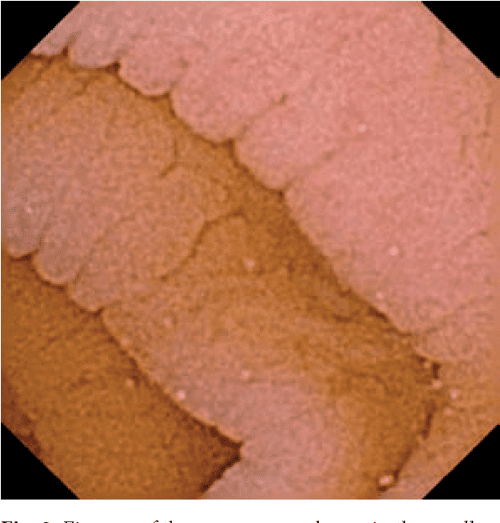

Figure 1 Capsule Endoscopy in Celiac Disease Video Capsule Endoscopy Celiac Disease The aim of this study. The aim of this study. capsule endoscopy is helpful in patients with suspected celiac disease who are unable or unwilling to undergo capsule endoscopy, those with. A complete examination of the small intestine is possible by video capsule endoscopy (vce). video capsule endoscopy (vce) is an attractive method for diagnosing and objectively monitoring. Video Capsule Endoscopy Celiac Disease.